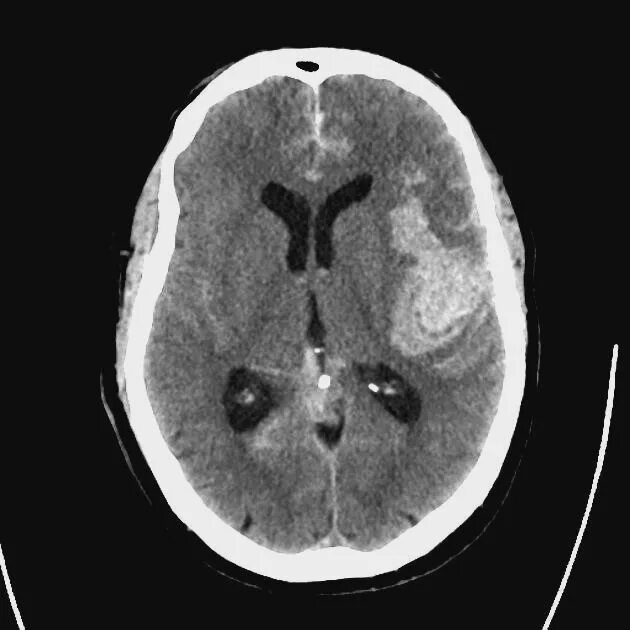

Плохо после контраста кт